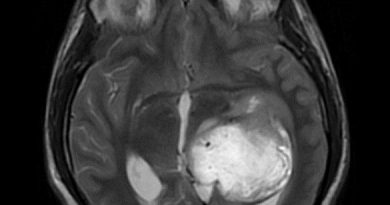

45 yaş, K

4 yıl önce akut sağ hemiparezi, konuşma bozukluğu ve dış merkezde serebellar iskemi tanısı ile ASA kullanımı öyküsü

Konuşma bozukluğu, yersiz gülme ve ağlama atakları, denge kaybı ve uyuşmaları devam ediyor

CADASIL

CADASIL SENDROMU